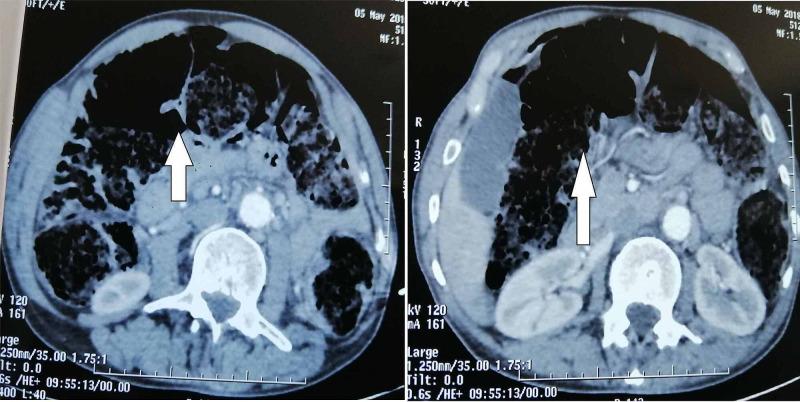

Intestinal tuberculosis is a frequent disease in developing countries, causing considerable morbidity and mortality. However, tuberculosis of the colon is rarer, and it also appears to be more common in immunosuppressed patients. We report the case of a 71-year-old immunocompetent man who was admitted to the emergency department with an acute abdomen and features of perforation peritonitis. A sigmoid perforation on cancer was suspected on computed tomography (CT) scan and surgical exploration. A standard sigmoidectomy with end colostomy (Hartmann's procedure) and peritoneal toileting was done. The pathological assessment of the surgical specimen revealed the sigmoid colon tuberculosis, complicated by perforation and peritonitis. Thus, the unexpected diagnosis of sigmoid colon tuberculosis was only made after the histopathological examination. Then, he received anti-tuberculosis treatment for six months. Therefore, a complete colonoscopy was performed at the end of the treatment, which returned to be normal. Thereafter, the restoration of intestinal continuity was performed. Colon tuberculosis is a rare disease and even rarer in people without immunodeficiency or on immunosuppressive therapy. If diverticulitis is the most common cause of sigmoid perforation, sigmoid perforation because of tuberculosis is extremely rare. However, an isolated primary sigmoid perforation of tubercular origin is not reported. We report this exceptional case of sigmoid colon tuberculosis complicated by perforation and generalized peritonitis to sensitize the medical team to its rare occurrence, which will be of paramount importance due to the increasing incidence of tuberculosis worldwide.

肠结核在发展中国家是一种常见疾病,会导致相当高的发病率和死亡率。然而,结肠结核较为罕见,在免疫功能低下的患者中似乎更为常见。我们报告一例71岁免疫功能正常的男性病例,该患者因急腹症和穿孔性腹膜炎特征被收入急诊科。计算机断层扫描(CT)和手术探查怀疑为癌性乙状结肠穿孔。进行了标准的乙状结肠切除术加结肠造口术(哈特曼手术)和腹腔清理。手术标本的病理评估显示为乙状结肠结核,并发穿孔和腹膜炎。因此,直到组织病理学检查后才意外诊断出乙状结肠结核。随后,他接受了六个月的抗结核治疗。治疗结束时进行了全结肠镜检查,结果恢复正常。此后,进行了肠道连续性恢复手术。结肠结核是一种罕见疾病,在无免疫缺陷或未接受免疫抑制治疗的人群中更为罕见。如果憩室炎是乙状结肠穿孔最常见的原因,那么结核导致的乙状结肠穿孔极为罕见。然而,尚未有孤立的原发性结核性乙状结肠穿孔的报道。我们报告这例罕见的乙状结肠结核并发穿孔和弥漫性腹膜炎的病例,以提高医疗团队对其罕见发生情况的认识,鉴于全球结核病发病率不断上升,这一点至关重要。